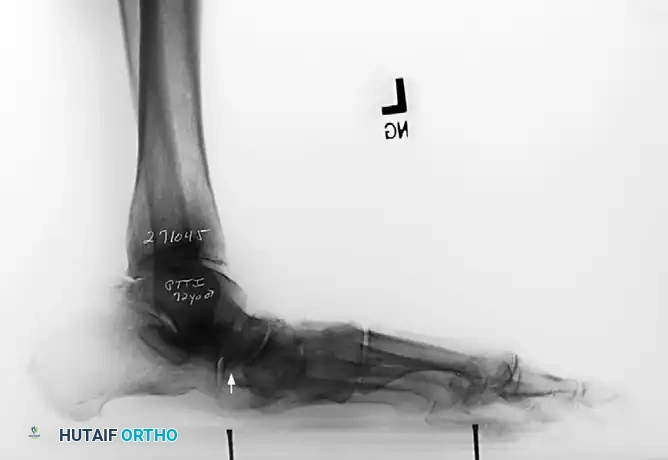

- Lateral View: Assess the medial longitudinal arch.

- Meary's Angle: The intersection of the longitudinal axis of the talus and the first metatarsal. An angle >4 degrees indicates arch collapse.

- Calcaneal Pitch: Decreased in flatfoot deformity.

- Lateral Tibial-Calcaneal Angle: Arangio et al. demonstrated this angle is a sensitive method for quantifying Achilles tendon contracture in adult-acquired flatfoot.

Measurement of the standing lateral tibial-calcaneal angle, utilized to quantify Achilles contracture.